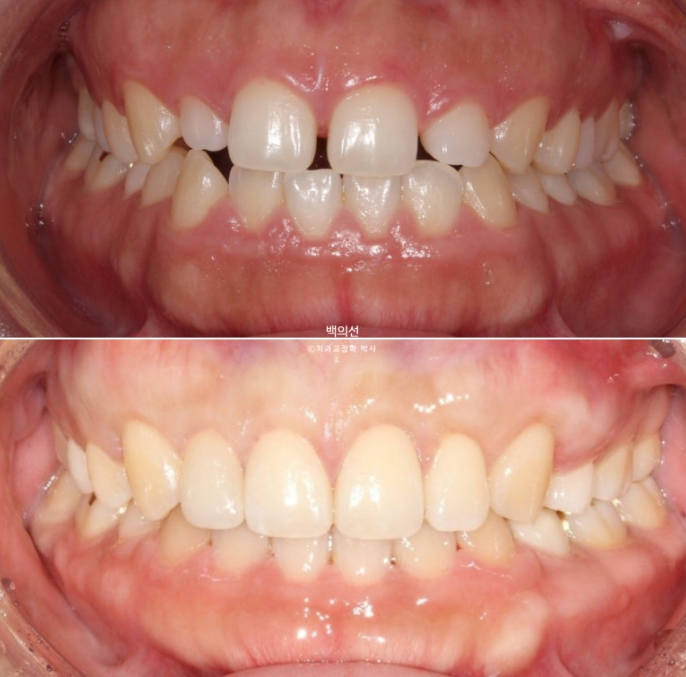

치아교정으로 인상을 드라마틱 하게 바꿀 수 있는 교정은 크게 두가지 입니다.

첫번째는 뭐니뭐니해도 돌출입 교정입니다.

두 번째는 거미스마일 교정입니다.

여기에 상악 전체치열 함입교정까지 더해 아래턱의 자가회전까지 일으킨다면 교정만으로도 양악수술 못지 않은 드라마틱한 결과가 탄생합니다.

2년 전 교정치료를 위해 오신 환자분입니다.

고치고 싶은 것은 세가지 입니다.

벌어짐

비대칭

무턱

아래턱이 좌측으로 틀어져 있는 골격적 비대칭이 있고 앞니 중심선도 어긋나 있습니다.

드디어 25년 7월, 2년의 교정치료를 마무리 합니다.

23.07~25.07

비대칭으로 인해 어긋났던 중심선이 맞아졌습니다.

교정만으로 턱뼈의 비대칭을 바꿀 순 없지만 최소한 치아중심선은 정확히 맞춰줄 수 있습니다.

교정 후 사진에서 앞니 교합이 다소 깊게 물리는 게 보이시죠?

의도한 부분이며 초진 시 앞니 물리는 게 얕으면, 재발을 고려하여 정상보다 좀 더 깊게 물리게 마무리 하는 게 좋습니다.

교정이 끝난 후 재발을 어느정도 고려한 과수정 즉 overcorrection의 개념은 치료에서 아주 중요하죠.

어금니 교합관계는 좌우 모두 1급 입니다.